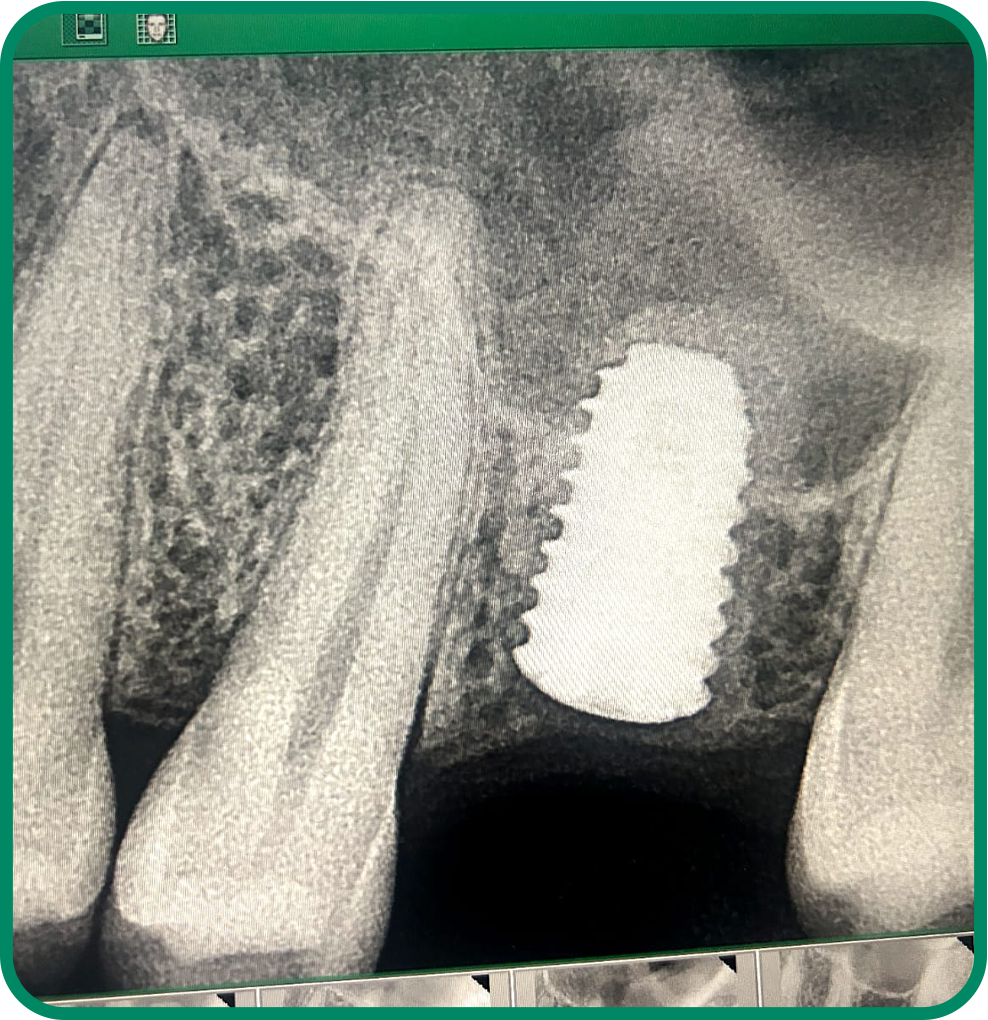

Dental Implants

Permanent tooth replacement solutions that restore natural function, strength, and appearance while improving confidence and long-term oral health.